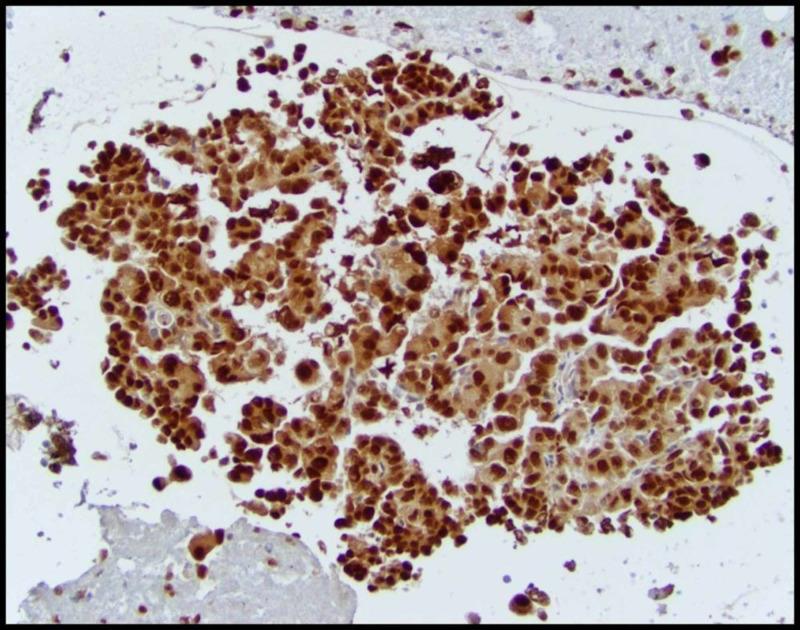

Renal cell carcinoma (RCC) can present with a myriad of clinical symptoms and signs. It is also notorious for its initial presentation with distant metastasis. We report a case of a 42-year-old male diagnosed with papillary RCC (PRCC) presenting with pleural and nodal metastases in the absence of a radiographically-detected tumor primary. PRCC was diagnosed on immunohistochemical analysis of the tissue from the pleura and mediastinal lymph nodes and confirmed by gene expression profiling studies. As per treatment guidelines for metastatic RCC, the patient was started on sunitinib with evidence of disease progression after two cycles and palliative care approach was recommended due to rapidly declining performance status. Prospective data on the optimal management of metastatic PRCC are lacking, but drugs used are similar to the treatment of clear cell carcinomas (vascular endothelial growth factor (VEGF) tyrosine kinase inhibitors, mammalian target of rapamycin inhibitors) and checkpoint inhibitors. Further molecular study of these rare tumors is warranted to detect drivers of oncogenesis and identify targets for therapeutic intervention.

摘要